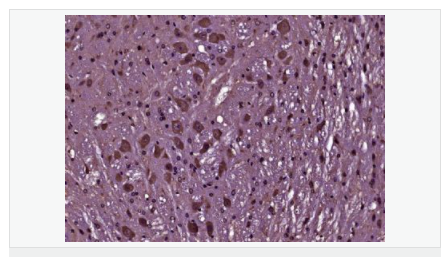

| 產(chǎn)品應(yīng)用 | WB=1:500-2000 ELISA=1:5000-10000 IHC-P=1:100-500 IHC-F=1:100-500 Flow-Cyt=1μg/Test IF=1:100-500 (石蠟切片需做抗原修復(fù)) not yet tested in other applications. optimal dilutions/concentrations should be determined by the end user. |

| 產(chǎn)品介紹 | BCL2 is an integral outer mitochondrial membrane protein that blocks the apoptotic death of some cells such as lymphocytes. Constitutive expression of BCL2, such as in the case of translocation of BCL2 to Ig heavy chain locus, is thought to be the cause of follicular lymphoma. Two transcript variants (alpha and beta) produced by alternate splicing, differ in their C-terminal ends. BCL2 suppresses apoptosis in a variety of cell systems including factor-dependent lymphohematopoietic and neural cells. It regulates cell death by controlling the mitochondrial membrane permeability. It appears to function in a feedback loop system with caspases. BCL2 inhibits caspase activity either by preventing the release of cytochrome c from the mitochondria and/or by binding to the apoptosis-activating factor (APAF1). It can form homodimers, and heterodimers with BAX, BAD, BAK and BclX(L). Heterodimerization with BAX requires intact BH1 and BH2 domains, and is necessary for anti-apoptotic activity. Function: Suppresses apoptosis in a variety of cell systems including factor-dependent lymphohematopoietic and neural cells. Regulates cell death by controlling the mitochondrial membrane permeability. Appears to function in a feedback loop system with caspases. Inhibits caspase activity either by preventing the release of cytochrome c from the mitochondria and/or by binding to the apoptosis-activating factor (APAF-1). Subunit: Forms homodimers, and heterodimers with BAX, BAD, BAK and Bcl-X(L). Heterodimerization with BAX requires intact BH1 and BH2 motifs, and is necessary for anti-apoptotic activity. Interacts with EI24 (By similarity). Also interacts with APAF1, BBC3, BCL2L1, BNIPL, MRPL41 and TP53BP2. Binding to FKBP8 seems to target BCL2 to the mitochondria and probably interferes with the binding of BCL2 to its targets. Interacts with BAG1 in an ATP-dependent manner. Interacts with RAF1 (the 'Ser-338' and 'Ser-339' phosphorylated form). Interacts (via the BH4 domain) with EGLN3; the interaction prevents the formation of the BAX-BCL2 complex and inhibits the anti-apoptotic activity of BCL2. Interacts with G0S2; this interaction also prevents the formation of the anti-apoptotic BAX-BCL2 complex. Subcellular Location: Mitochondrion outer membrane; Single-pass membrane protein. Nucleus membrane; Single-pass membrane protein. Endoplasmic reticulum membrane; Single-pass membrane protein. Tissue Specificity: Expressed in a variety of tissues. Post-translational modifications: Phosphorylation/dephosphorylation on Ser-70 regulates anti-apoptotic activity. Growth factor-stimulated phosphorylation on Ser-70 by PKC is required for the anti-apoptosis activity and occurs during the G2/M phase of the cell cycle. In the absence of growth factors, BCL2 appears to be phosphorylated by other protein kinases such as ERKs and stress-activated kinases. Phosphorylated by MAPK8/JNK1 at Thr-69, Ser-70 and Ser-87, wich stimulates starvation-induced autophagy. Dephosphorylated by protein phosphatase 2A (PP2A). Proteolytically cleaved by caspases during apoptosis. The cleaved protein, lacking the BH4 motif, has pro-apoptotic activity, causes the release of cytochrome c into the cytosol promoting further caspase activity. Monoubiquitinated by PARK2, leading to increase its stability. DISEASE: Note=A chromosomal aberration involving BCL2 has been found in chronic lymphatic leukemia. Translocation t(14;18)(q32;q21) with immunoglobulin gene regions. BCL2 mutations found in non-Hodgkin lymphomas carrying the chromosomal translocation could be attributed to the Ig somatic hypermutation mechanism resulting in nucleotide transitions. Similarity: Belongs to the Bcl-2 family. SWISS: P49950 Gene ID: 596 Database links: Entrez Gene: 596 Human Entrez Gene: 12043 Mouse Omim: 151430 Human SwissProt: P10415 Human SwissProt: P10417 Mouse Unigene: 150749 Human Unigene: 257460 Mouse Unigene: 9996 Rat Important Note: This product as supplied is intended for research use only, not for use in human, therapeutic or diagnostic applications. |